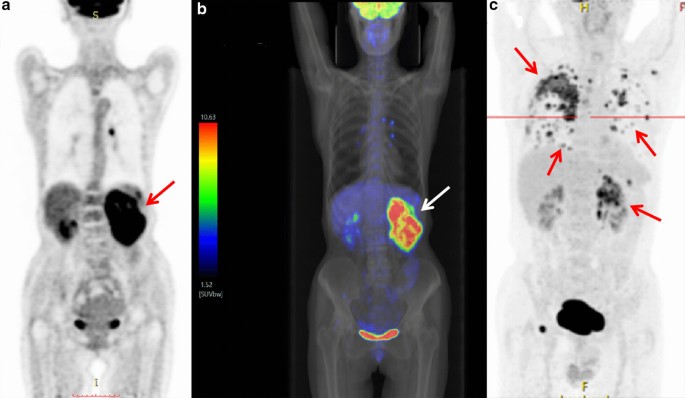

PET/CT findings

PET/CT detected increased renal radioactivity intake in two patients (Fig. 6a–c). The maximum SUV values were 14.9 and 14.3 (the maximum SUV values of the normal renal parenchyma were 3.6 and 2.9). CT detected the corresponding sites as isodense masses. In one case, the CT scan showed an unclear lesion. However, PET/CT showed significant metabolic activity with extensive systemic metastases, including mediastinal, retroperitoneal lymph node, homolateral adrenal gland, bilateral lungs, bilateral pleura, right ribs, left scapula, and right pubic symphysis metastases.

Case 11: a PET/CT images of renal CDC show significant concentration in the left kidney area with a maximum SUV of 14.9 (arrow). b PET/CT and simulated X-ray fusion images show significant concentration in the left kidney region with a maximum SUV of 14.9 (arrow). c Case 3: PET/CT image shows increased metabolism of the left renal CDC with extensive systemic metastases including mediastinal, retroperitoneal lymph node metastasis, homolateral adrenal gland, bilateral lungs, bilateral pleura, right ribs, left scapula, and right side pubic symphysis (arrows)

Most RCCs have a low FDG metabolism and are similar to the normal renal parenchyma. 18F-FDG PET has certain limitations in the detection and diagnosis of common renal cancer [24]. Because CDC is rare, there is little information on PET performance in the literature. Ye et al. reported a case of CDC with a maximum diameter of 4.6 cm in the right kidney. The SUVmax of PET was 7.0 [25]. Two patients in our group underwent PET/CT examination, and the primary lesions were highly metabolic, with SUVmax values of 14.9 and 14.3, respectively. One of the PET/CT images showed a higher metabolism in the lymph nodes, lungs, pleura, and multiple bone metastases, which was consistent with the HU and other studies [26]. Compared with other common renal cancer pathological types (such as clear cell carcinoma), CDC is characterized by high invasiveness and a poor prognosis, and it frequently shows high FDG uptake. 18F-FDG PET/CT is effective for the diagnosis of renal tumor metastasis. Besne et al. showed that the 5-year survival rate of patients with distant metastasis of urinary tumors is 0–20%. However, resection of isolated metastases increases the 5-year survival rate to 25–50% [27]. Therefore, early detection of metastases is essential. Safaei et al. [28] reported that the sensitivity and specificity of PET for detecting renal cell carcinoma metastases are 87% and 100%, respectively. Majhail et al. analyzed the biopsy or surgical resection samples from 36 metastatic lesions in 24 patients with RCC. The results showed that the specificity and positive predictive value of 18F-FDG PET/CT for distant metastasis were 100% [29]. In this study, PET/CT of the lymph nodes showed no metastasis after surgical resection. The diagnosis of lymph node metastasis by PET/CT needs to be further investigated.